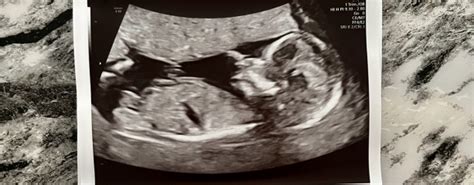

Hey guys! Expecting a baby is such an exciting time, but it can also come with a whole lot of anxiety, right? One of the most significant milestones during pregnancy is the 20-week scan, also known as the anatomy scan. This ultrasound gives you a detailed look at your baby’s development and helps to identify any potential issues. But what happens when the scan reveals something unexpected? It’s natural to feel worried, and many parents turn to online communities like Reddit and Mumsnet to share their experiences and seek support. Let’s dive into what you might find on these platforms regarding bad news at the 20-week scan and how common these situations actually are.

The 20-week scan , or anatomy scan, is a detailed ultrasound examination usually performed between 18 and 22 weeks of pregnancy. Its primary goal is to assess the baby’s physical development and screen for any structural abnormalities. During the scan, the sonographer will carefully examine various parts of the baby’s body, including the brain, heart, spine, limbs, and organs. They’ll also check the placenta and amniotic fluid levels. The scan provides crucial information about the baby’s health, allowing healthcare providers to plan for any necessary interventions or specialized care after birth.